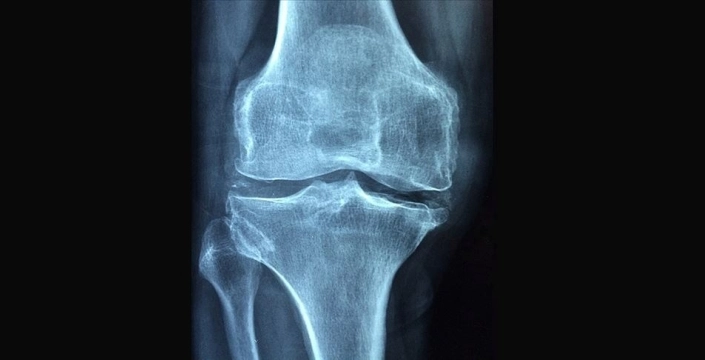

Polonyalı bilim insanları, kırık kemik tedavisinde çığır açacak bir buluşa imza attı. Geliştirilen yenilikçi biyomalzeme, kırık kemiğe enjekte edilerek, ameliyatlarda kullanılan plak ve vidalara gerek kalmadan iyileşmeyi sağlıyor. TVP World’ün cumartesi günkü haberine göre, bu yöntem tedavi sürecini hızlandıracak ve maliyetleri düşürecek.

Szczecin kentindeki Batı Pomeranya Teknoloji Üniversitesi’nde iki yıllık bir araştırmanın ürünü olan polimer, vücut içinde sertleşerek kırığı sabitliyor. Üniversiteden Profesör Miroslawa El Fray, bu yeni tekniğin özellikle kış aylarında Polonya’da sıkça görülen bilek kırıkları için umut vadettiğini belirtti. Polimerin biyobozunur özellikte olduğunu vurgulayan El Fray, 'Kırık bölgesine tek seferde uygulanacak, sonrasında çıkarılmasına gerek olmayacak. Kemiğin iyileşme sürecini tetikleyecek ve ardından vücutta tamamen yok olacak.' diye konuştu.

Araştırmacılar, bu teknolojinin yaygınlaşmasıyla daha hızlı ve maliyet etkin bir kırık kemik tedavisi sağlanmasını bekliyor. Ancak, biyomalzeme henüz patentlenmemiş ve ticarileştirilmemiştir.